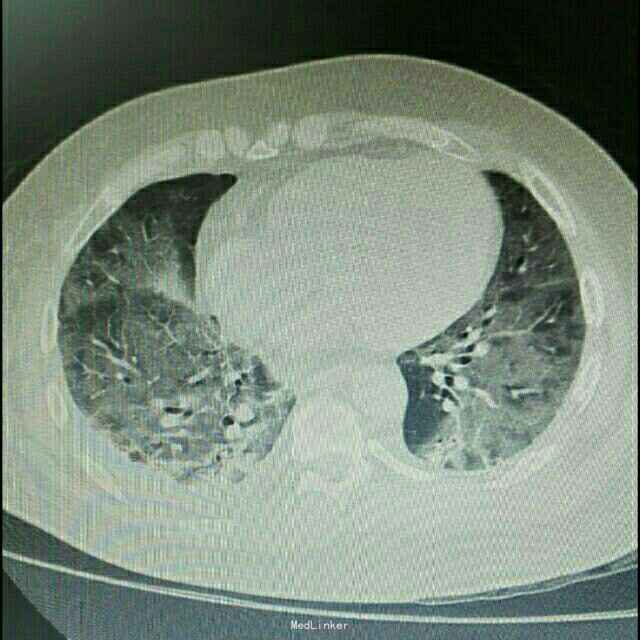

主诉:肾移植术后2月,发热、咳嗽5天 病史:患者男,45岁,因尿毒症于2月前在外院行异体肾移植术,手术过程顺利,术后恢复良好,移植肾功能稳定,服用FK506+MMF+Pred免疫抑制维持治疗。患者术后未规律门诊随诊,有情况变化时常电话联系行手术的医院,在术后免疫抑制剂服用剂量较大,为MMF1gBid+FK506 3.5mgBid+Pred25mgQd,其中FK506平时维持的浓度约10ng/ml。5天前开始出现发烧,最高体温38.8℃,自服“降温药”后体温可下降,伴咳嗽,无胸闷气促,无诉其他不适。

辅助检查:患者入院后症状进行性加重,入院2日后出现胸闷、气促,动脉血气分析提示氧分压为59mmHg,胸部CT提示双肺严重弥漫性炎症。

诊断:肺部感染;异体肾移植状态 治疗:患者入院后积极抗感染治疗,检查胸部CT和血气分析后给予吸氧等对症治疗,抗感染方案为泰能+伏立康唑+科赛斯+更昔洛韦,并停用所有口服免疫抑制剂,改为甲强龙40mgQd静脉滴注,患者治疗后肺部感染无明显好转,2日后转入ICU进一步治疗。